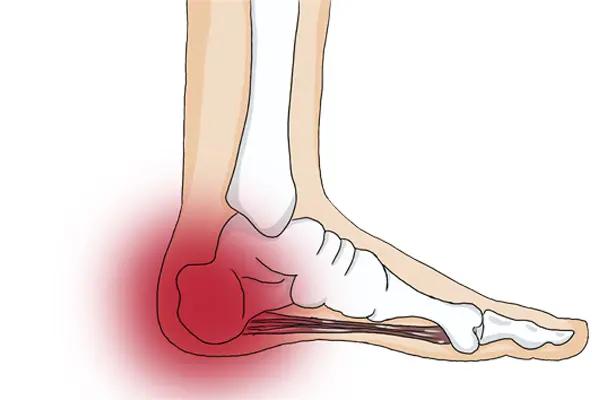

本人双侧足跟剧痛,缠身近一年,遍寻医方、试尽偏方,皆难除根!每一步行走如踏针毡,日常站立苦不堪言,身心俱疲、备受煎熬,生活几近受困!今天终于卧床了。

躬身求救!凡有过足跟痛康复经历、手握有效治痛良方、知晓靠谱就医门路者,望不吝赐教、慷慨分享!点滴善举,皆能解我燃眉之苦,欢迎留言,帮我去除脚后跟疼。感激留言。

本人双侧足跟剧痛,缠身近一年,遍寻医方、试尽偏方,皆难除根!每一步行走如踏针毡,日常站立苦不堪言,身心俱疲、备受煎熬,生活几近受困!今天终于卧床了。

躬身求救!凡有过足跟痛康复经历、手握有效治痛良方、知晓靠谱就医门路者,望不吝赐教、慷慨分享!点滴善举,皆能解我燃眉之苦,欢迎留言,帮我去除脚后跟疼。感激留言。